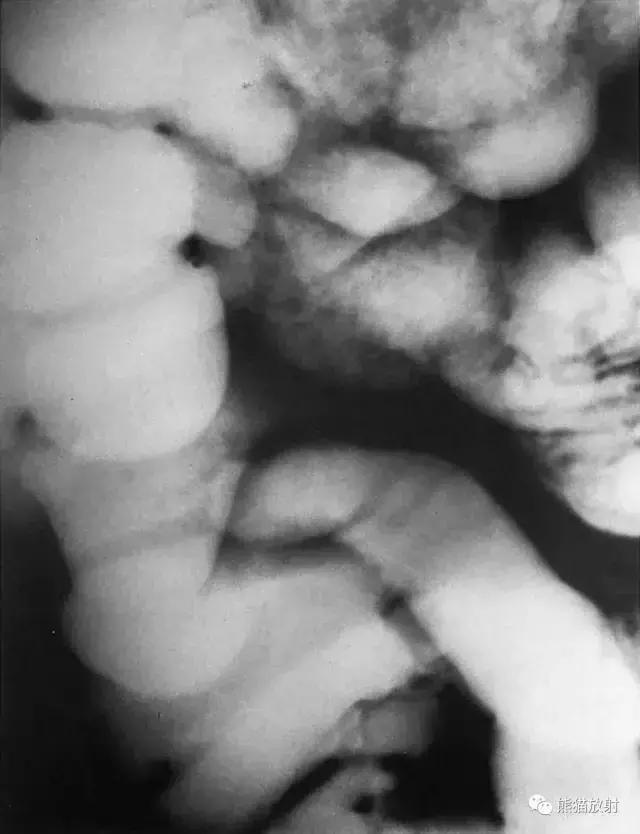

十一、直肠

图21 直肠造影

图22 直肠解剖示意图。1 直肠乙状结肠连接部,2 骶骨,3 直肠后间隙,4 直肠横襞,5 股骨头,6 直肠壶腹部,7 尾骨,8 肛门直肠交界处